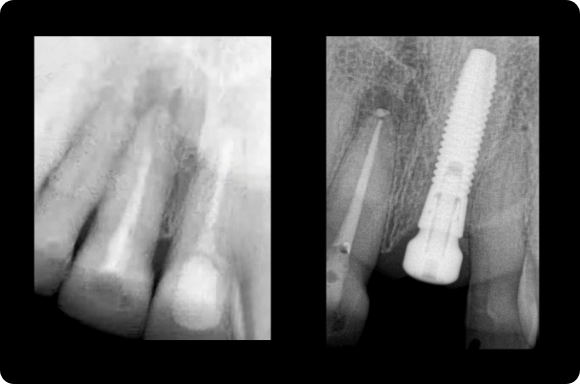

Ce cours de niveau maîtrise aborde à la fois la prévention et la gestion des complications chirurgicales et restauratrices. Dans le domaine chirurgical, la présentation se concentre sur l’échec précoce de l’implant et la maladie péri-implantaire ultérieure. Les concepts prothétiques comprendront la conception de prothèses préventives, le retrait des vis/piliers et un séquençage qui reconnaît l’importance de l’expérience du patient.

Le programme consacré à l’implantologie est une série de cours interactifs basés sur les procédures qui utilisent des cas individuels pour enseigner le traitement actuel des implants. Cette approche est contraire à l’éducation dentaire conventionnelle qui se concentre davantage sur les sujets et la théorie didactiques. L’objectif de cette approche pédagogique est de mettre en évidence les patients et les procédures rencontrés dans la pratique clinique quotidienne, où les concepts les plus importants sont observés et discutés dans de multiples scénarios cliniques.

Sur la base des procédures : Cours de niveau 6

Maîtrise : Cours de niveau 8